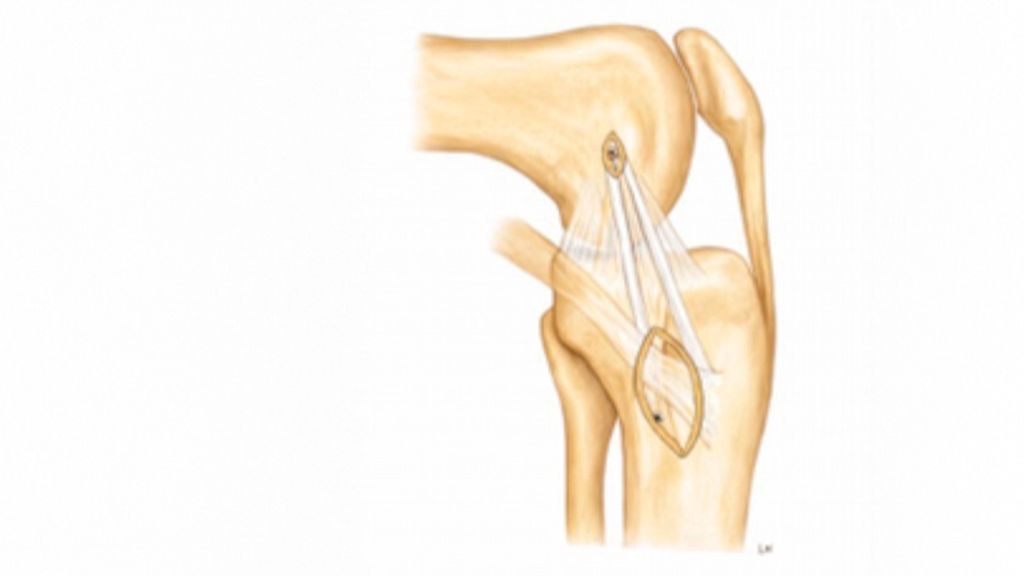

Arthroskopische Instabilitätszeichen: „floating meniscus“ und „drive-through sign“

In einer Level-I-Studie an Patient:innen mit kombinierten VKB- und Grad-II-MCL-Verletzungen (nach Fetto und Marshall) und „Floating-Meniskus-Zeichen“ zeigte die Patientengruppe nach MCL-Augmentation mittels gestielter autologer Gracilis-Sehne signifikant weniger VKB-Revisionen, eine geringere residuale MCL-Laxität sowie bessere patient:innenberichtete Outcome-Scores nach 24 Monaten im Vergleich zu Patient:innen mit isolierter VKB-Rekonstruktion und konservativ behandeltem MCL. Die Abbildung 1 zeigt das „Floating-Meniskus-Zeichen“, ein arthroskopisches Zeichen der medialen Instabilität, bei dem sich der mediale Meniskus vom tibialen Plateau abhebt, infolge einer meniskotibialen Läsion des tiefen Innenbandes. Aufgrund einer zusätzlichen Läsion des oberflächlichen Längsbandes kommt es zu einer medialen Gelenköffnung, die als „medial drive-through sign“ bezeichnet wird.

Anteromediale Tenodese

Die anteromediale Tenodese unter Verwendung der gestielten Gracilis- oder Semitendinosus-Sehne dient der Augmentation bzw. Rekonstruktion sowohl des tiefen als auch des oberflächlichen medialen Kollateralbandes (d/sMCL) über zwei funktionelle Bündel. Abhängig vom zugrunde liegenden Verletzungsmuster kann der Eingriff über einen minimalinvasiven oder einen offenen Zugang durchgeführt werden. Die Technik eignet sich bei akuten Eingriffen in Kombination mit einer MCL-Naht bzw. Refixation im Sinne eines „Bio-Brace“. Darüber hinaus kann sie bei chronischen Fällen mit leichter bis moderater anteromedialer Instabilität mit oder ohne VKB-Rekonstruktion durchgeführt werden. Der Ablauf eines solchen Eingriffes ist wie folgt: Die Sehne wird proximal mittels offenen Sehnenstrippers entnommen, während die tibiale Insertion erhalten bleibt. Die femorale Fixation der gedoppelten Sehne erfolgt im hinteren Anteil des nativen Ansatzes des oberflächlichen Längsbandes, während das freie Sehnenende im Zentrum der distalen tibialen Insertionsstelle des oberflächlichen medialen Kollateralbandes fixiert wird. Eine detaillierte Beschreibung der Operationstechnik ist über den QR-Code (Abb. 2,3) als Videoanleitung abrufbar.1